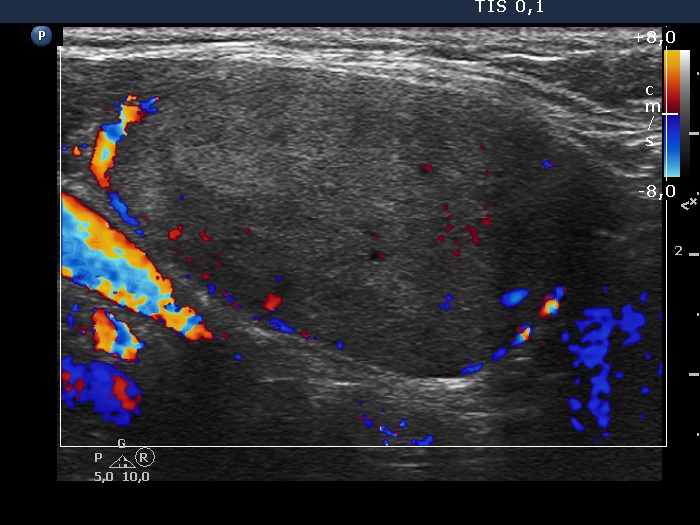

Left lobe longitudinal scan, color Doppler mode. The nodule presents perinodular blood flow.

Right lobe, longitudinal scan